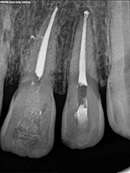

Root Canal Cases